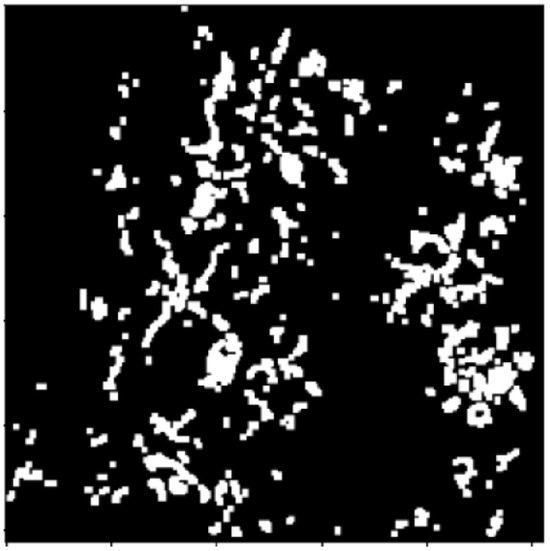

2.2.3. Distance Transform

2.3. Segmentation